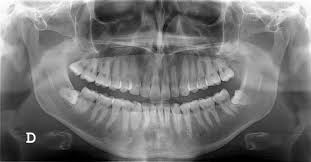

Without socket preservation, the bone quickly resorbs resulting in 30–60% loss in bone volume in the six months after dental extraction. The jaw bone will never revert to its original shape once bone is lost and tissue contour has changed.

The severity of the healing pattern may pose a problem for the clinician in 2 ways: it creates an esthetic problem in the fabrication of an implant-supported restoration or a conventional prosthesis; and it may make the placement of an implant challenging if not unfeasible.

The placement of an implant at a site with a thin crestal ridge (e.g., postextraction ridge) could result in a significant buccal dehiscence. Thus, it seems prudent to prevent alveolar ridge destruction and make efforts to preserve it during extraction procedures.